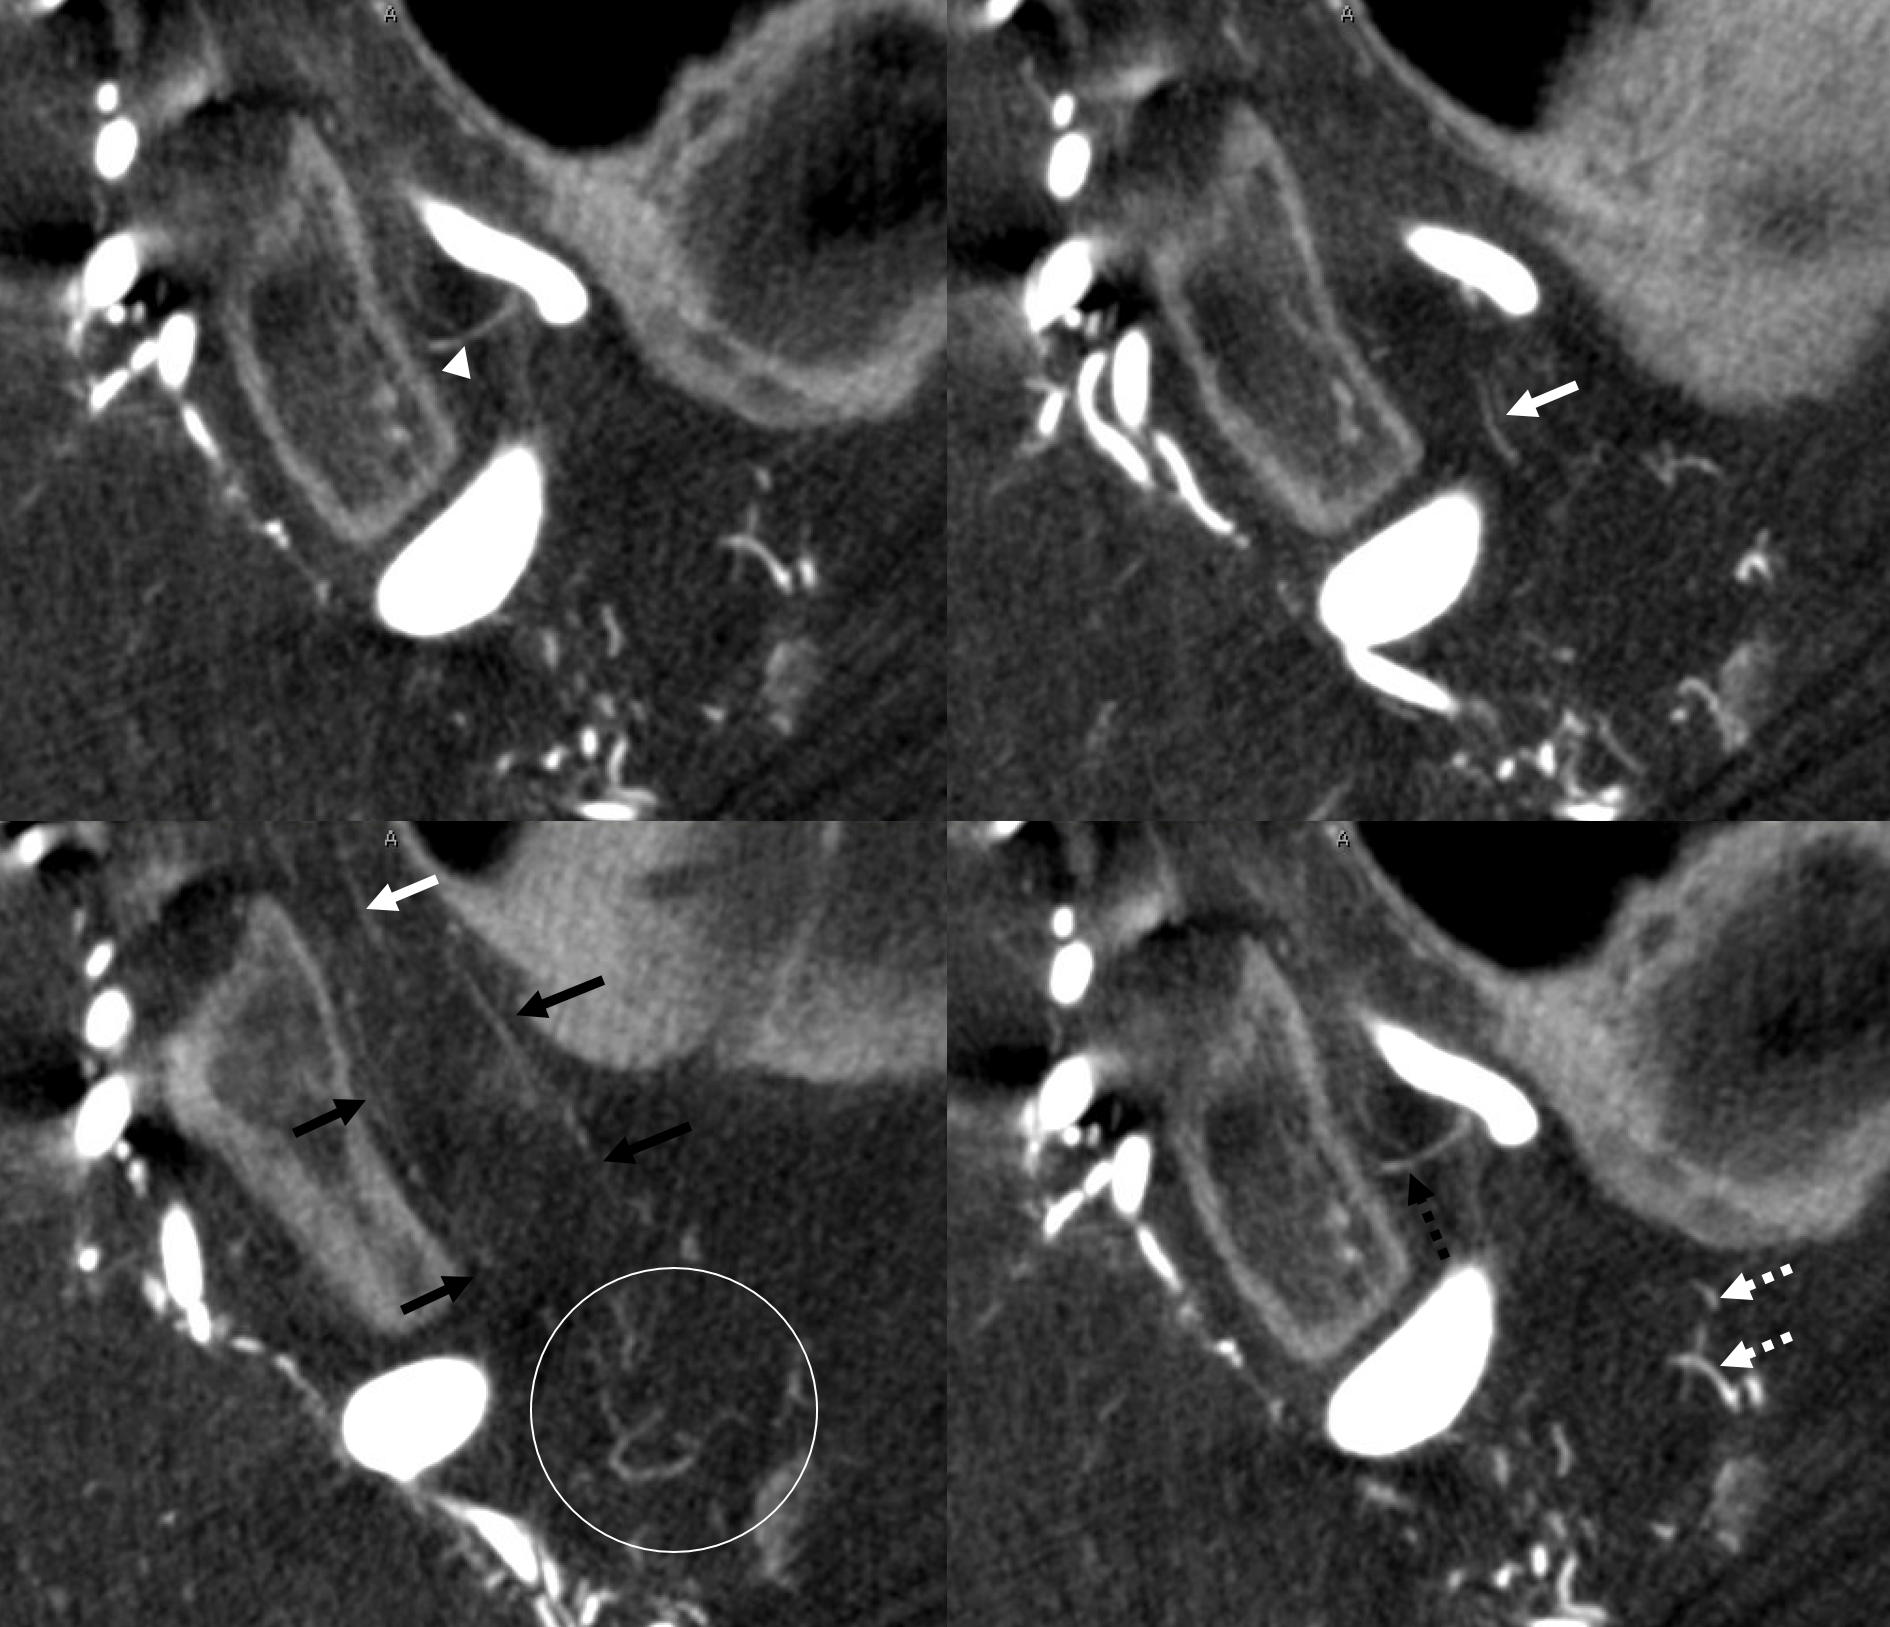

DSA — yes, they do exist on DSA also. A slight contralateral oblique is probably best — to throw them off other vessels. Here, an LAO of right ICA injection shows a farily promenent superior hypophyseal (white arrow, with an infundibulum), supplying the pituitary stalk (black arrwos). Also seen is inferior hypophyseal (dashed white arrow) supply of the posterior pituitary (dashed black arrow)

Supply of the Hypophysis and Balance

As always neuroangio is about balance. There may be one or more superior hypophyseal arteries. Usually one is visible by cone beam/flat panel CT. Sometimes more than two. Here there are 3. Nicely shown is supply of the stalk (open arrow). There is also likely contribution to the optic chiasm, which is of course very important. The inferior hypophyseal branches (dashed arrow) from the MHT support the posterior pituitary. The ILT is hypoplastic, with lateral branches of the MHT (white arrowhead) heading towards the meckel cave and the recurrent branch along the tentorial edge (black arrowhead) supplying territory normally done by the ILT

Without labels